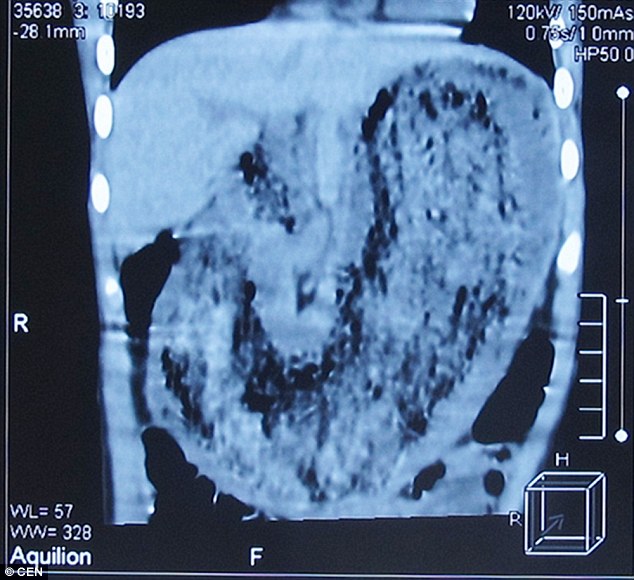

Bé Liuniu Liang, 8 tuổi đã được bố mẹ đưa tới bệnh viện sau khi phát hiện em bị sụt cân nhanh chóng. Các bác sĩ đã tiến hành kiểm tra và vô cùng ngạc nhiên khi phát hiện có một cuộn tóc nặng 2kg trong dạ dày của bé gái.

Tiến sĩ Zhang Shufeng, người đã điều trị cho cô bé còn cho biết, trong dạ dày của em còn có móng tay, mảnh vải quần áo. Những thứ này khiến cho cô bé có cảm giác buồn nôn, không thể ăn uống và giảm cân nhanh chóng.

Hình ảnh cho thấy trong dạ dày bé gái có cả móng tay và vải quần áo. |